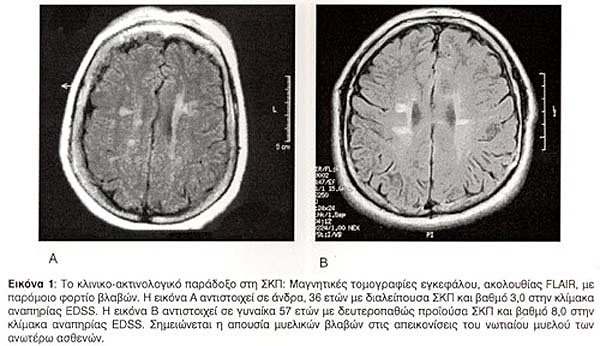

Η συσχέτιση του βαθμού αναπηρίας, όπως αυτός προσδιορίζεται από την κλίμακα EDSS, με τη βαρύτητα των βλαβών στη συμβατική μαγνητική τομογραφία έχει βρεθεί να είναι χαμηλή27,28, έως οριακή29. Η περιγραφείσα δυσαρμονία μεταξύ του φορτίου των βλαβών στη συμβατική μαγνητική τομογραφία και της κλινικής εικόνας αποτελούν την πρώτη όψη του "κλινικο-ακτινολογικού παραδόξου" της ΣΚΠ (Εικόνα 1, Εικόνα 2). Η δεύτερη όψη του παραδόξου, όπως έχει ήδη περιγραφεί, αφορά στους ασθενείς που εμφανίζουν βλάβες σε οξεία φάση στη μαγνητική τομογραφία χωρίς συνοδό κλινική έξαρση της νόσου. Η τρίτη όψη αφορά στους ασθενείς με πρωτοπαθώς προϊούσα ΣΚΠ. Στις περιπτώσεις αυτές η ανεύρεση ολιγάριθμων βλαβών στη μαγνητική τομογραφία, παρά τη μεγάλη κλινική αναπηρία, αποτελεί συνήθως τον κανόνα (Εικόνα 3).

Η πιο σημαντική ιδιότητα ενός δείκτη-υποκατάστατο θεωρείται η ικανότητα του να αντικατοπτρίζει μια κλινικά σημαντική παράμετρο. Αδιαμφισβήτητα, στη ΣΚΠ η σημαντικότερη κλινική παράμετρος είναι η ανάπτυξη μόνιμης αναπηρίας. Τα τελευταία χρόνια έχει καταστεί σαφές ότι η συσχέτιση της συμβατικής μαγνητικής τομογραφίας με την αναπηρία είναι σε γενικές γραμμές περιορισμένη5. Η διαπίστωση αυτή αποτελεί την πρώτη όψη του "κλινικο-ακτινολογικού παραδόξου" στη ΣΚΠ. Η δεύτερη όψη αφορά στη συχνή παρουσία ενεργών βλαβών στη μαγνητική τομογραφία χωρίς συνοδό κλινική έξαρση της νόσου. Η τρίτη και τελευταία όψη του παραδόξου αφορά στον χαμηλό αριθμό και όγκο βλαβών στην Τ2 ακολουθία που παρατηρείται στην πρωτοπαθώς προϊούσα ΣΚΠ, παρά τη συγκριτικά μεγαλύτερη αναπηρία των ασθενών αυτών.